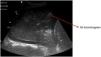

Alveolar consolidation or lung hepatization patternLung hepatization is described as a liver-like appearance of the consolidated lung seen at ultrasound exploration. This type of image is easier to visualize in supradiaphragmatic consolidations (Suppl. Fig. 6).